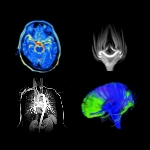

The image was done by myself collating figures available on the internet MRI, in Action! | Lab Tour

Do you want to discover one of the most powerful and safest ways scientists and doctor have developed and use to look inside materials, plants, insects, animals, and indeed the human body? Join researchers form the Interdisciplinary Centre for Magnetic Resonance at the School of Chemistry and Chemical Engineering of the University of Southampton to watch a live magnetic resonance imaging (MRI) experiment and learn about instrumentation and methodologies used to produce amazing MRI images. MRI is used as a painless routine exam that doctors use to look inside people to diagnose a variety of illnesses. It is also abundantly used in research laboratories around the world to study properties of materials, plants, animals and more. Join us and discover who are our little patients and help us provide them with a diagnosis.You may also like